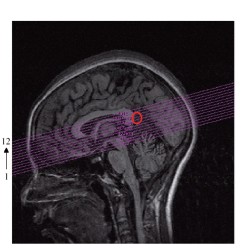

一九九八年,我們也用功能性磁造影(functional magnetic imaging,簡稱fMRI)技術測量了高橋小姐手指識字時大腦各部位的活動情形(如一○四頁圖2-15所示),並將大腦切割成十二條細長紫色線分隔的區間,包括視丘、松果體、胼胝體等部位。

圖2-15 手指識字時,用fMRI測量大腦各部位活動情形

![]() |

| 紅色部位是開天眼前後信號變化較大的部位。從第7張腦顯影片可看到,左腦聽覺部位有變化,第8張起,腦中央部位一些區域有很大的變化。 |

高橋一手操控按鈕,開天眼時按一下作為信號,幫助分析數據。

如右圖2-15下方顯影圖所示,上排是第五、六、七、八的四片區域;下排是第九、十、十一、十二的四片區域,以及開天眼前後信號變化圖,紅色部位是較大的變化。很明顯的是,從第七張左腦聽覺部位有變化,第八張起中央部位一些區域有很大的變化。

下圖2-16中,大腦藍色區塊內顯示的是第八片紅色區域實際信號的變化圖,右圖中的橘色是高橋舞小姐開天眼時按下的信號,總共開了兩次天眼,縱軸是fMRI信號在天眼打開時變化的百分比。

圖2-16 大腦藍色區塊內,開天眼前後的FMRI信號變化百分比

| 圖表中藍色區間為頭部稍微移動的區間,但與第一次開天眼時間無關。第二次開天眼時信號變化達到140%。 |

第二次開天眼時,她信號變化竟然達到百分之一百四十,遠高於一般正常信號變化百分之一到三的五十倍。第一次測量時,所有專家沒有人相信這個數據,都認為頭有動。但是經進一步分析發現她頭稍微移動的時間並非第二次開天眼的時間,如藍色區間顯示。後來第二次作實驗時,信號反應還是一樣巨大,才說服大家這是真的信號。一○四頁圖2-15第九、十片腦區雖然信號變化較小,但是還是比一般信號要大得多,所以我們初步判定天眼開的部位是在下圖2-17紅圈的位置,很接近大腦中後扣帶皮層(posterior cingulate cortex,簡稱PCC)部位。

圖2-17 開天眼時,fMRI信號反應最強區域

| 紅圈位置,為開天眼時的反應部位,似乎很接近大腦中的後扣帶皮層。 |